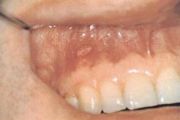

Crohni tõbi

limaskestal munajad moodustised (munakivi meenutavad)